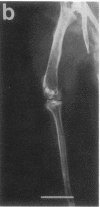

Studies were carried out on a line of transgenic mice that expressed an internally deleted COL2A1 gene and developed a phenotype resembling human chondrodysplasias (Vandenberg et al. 1991. Proc. Natl. Acad. Sci. USA. 88:7640-7644. Marked differences in phenotype were observed with propagation of the mutated gene in an inbred strain of mice in that approximately 15% of the transgenic mice had a cleft palate and a lethal phenotype, whereas the remaining mice were difficult to distinguish from normal littermates. 1-d- and 3-mo-old transgenic mice that were viable showed microscopic signs of chondrodysplasia with reduced amounts of collagen fibrils in the cartilage matrix, dilatation of the rough surfaced endoplasmic reticulum in the chondrocytes, and decrease of optical path difference in polarized light microscopy. The transgenic mice also showed signs of disturbed growth as evidenced by lower body weight, lower length and weight of the femur, decreased bone collagen, decreased bone mineral, and decreased resistance of bone to breakage. Comparisons of mice ranging in age from 1 d to 15 mo demonstrated that there was decreasing evidence of a chondrodysplasia as the mice grew older. Instead, the most striking feature in the 15-mo-old mice were degenerative changes of articular cartilage similar to osteoarthritis.